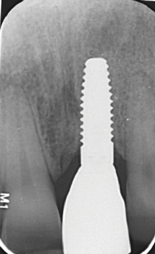

Fig 1. Titanium (left) and zirconia (right) implants.

Figure 1

Fig 8. Insertion of metal-free ceramic implant (4.2 mm x 12 mm) 8 weeks after extraction of hopeless tooth No. 9.

Figure 8

Fig 13. Radiograph after loading, showing solid bone remodeling within the machined implant neck area.

Figure 13